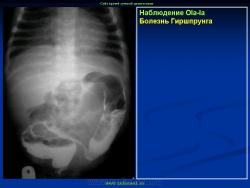

Варианты и аномалии развития толстой кишки.